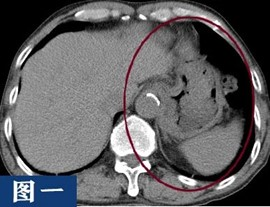

以上为同一个患者两次检查的结果,第一次没有喝水,胃没有充盈;第二次是喝水后,胃已充盈。大家可以很清楚的看到,没有充盈的胃腔且有食物残留,好似长了肿块一样,会干扰影像医生的诊断。

通过这个病例展示,患者做腹部CT检查前空腹及喝足量水是很有必要的。因腹腔内脏器较多,且大多数属于消化系统,有空腔脏器(胃、肠道、膀胱等),也有实质脏器(肝、胰腺、脾脏、肾脏等),由于缺乏天然对比,腹腔内的结构往往不能被清楚的分辨,水作为一种天然对比剂,可以增强组织与周围结构的对比度。通过喝水,胃肠道可以充分膨胀,使其内部结构更加清晰;此外,喝水还有助于减少胃肠道中气体的对图像的干扰,可以更好的帮助影像医生观察胃肠道的形态,有无异物或肿瘤等情况,减少误诊或漏诊的发生。